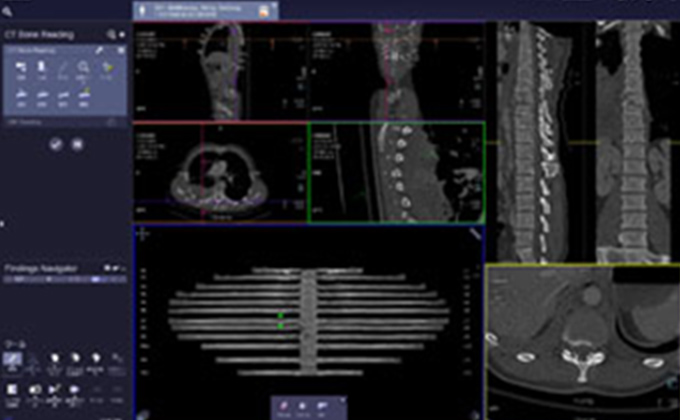

画像診断支援システム

シーメンス社のSyngo.Viaを導入し、スムーズで的確な読影と、シームレスな画像診断環境の構築を目指しています。

画像提供:シーメンス・ジャパン株式会社